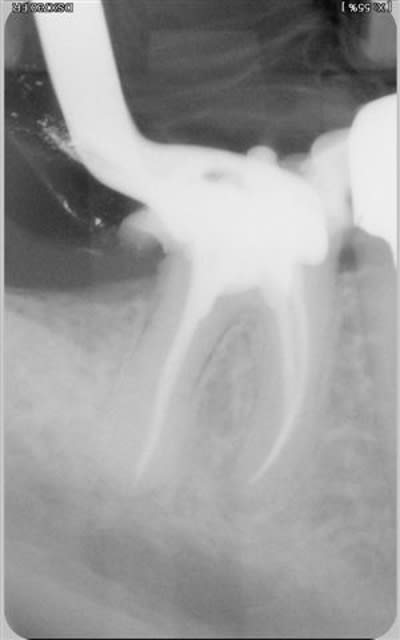

une 46:le pronostic?

35:decouverte fortuite sous un si joli inlay or que je l'ai rescellé(adieu CCC...)

et un puff:sniff!(j'essaye pourtant,stephane,j'essaye de les supprimer)

Effectivementm, la 46, pas sur qu'e;;e est le temps de cicatriser. Mais, l'echec sera d'origine paro non endodontique.

un excellent exemple de lesion endo paro. Traitement paro prevu ?